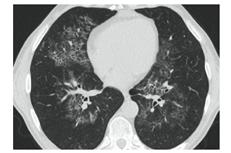

КТ имеет высокую чувствительность в выявлении изменений в легких, характерных для COVID-19. Применение КТ целесообразно для первичной оценки состояния ОГК у пациентов с тяжелыми прогрессирующими формами заболевания, а также для дифференциальной диагностики выявленных изменений и оценки динамики процесса. КТ позволяет выявить характерные изменения в легких у пациентов с COVID-19 еще до появления положительных лабораторных тестов на инфекцию с помощью МАНК. В то же время, КТ выявляет изменения легких у значительного числа пациентов с бессимптомной и легкой формами заболевания, которым не требуется госпитализация. Результаты КТ в этих случаях не влияют на тактику лечения и прогноз заболевания при наличии лабораторного подтверждения COVID-19. Поэтому массовое применение КТ для скрининга асимптомных и легких форм болезни не рекомендуется.

4. Все выявляемые при лучевых исследованиях признаки, включая КТ-симптомы, не являются специфичными для какого-либо вида инфекции и не позволяют установить этиологический диагноз. Вне клинической (эпидемической) ситуации они не позволяют отнести выявленные изменения к пневмонии COVID-19 и дифференцировать их с другими пневмониями и невоспалительными заболеваниями. Данные лучевого исследования не заменяют результаты обследования на РНК SARS-CoV-2. Отсутствие изменений при КТ не исключают наличие COVID-19 и возможность развития пневмонии после проведения исследования.